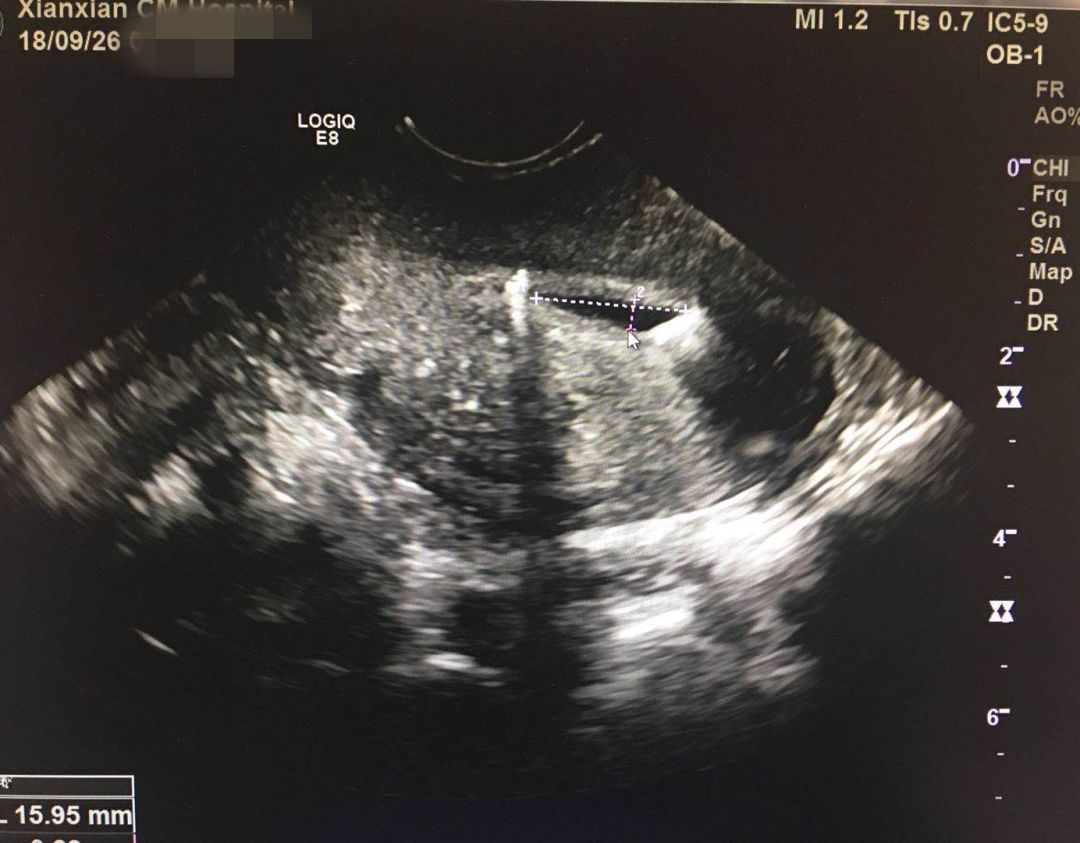

为此,我院新引进世界领先专业妇产彩超机GE-e8,和各大三级医院妇产科彩超同型号,是我县首台高端腔内彩超,此项技术是我院妇产超声诊断技术的又一进步。 由于经阴道彩超对于妇科疾病诊断有着腹部彩超无以伦比的优势,因此更多的妇科疾病建议选择阴道彩超。

阴道彩超也是超声的一种检查形式,又称腔内超声,是将超声探头放入阴道或者直肠进行超声检查的方法。

高频探头、分辨率高:经阴道彩超可以更加清晰的观察妇科方面的疾病, 经阴道超声与传统经腹部超声比较,探头几乎直接接触扫描器官,缩短了探头与被检查器官的距离,更大的提高图像分辨力。

图像清晰:对盆腔内微小包块及积液显示效果更满意,早期诊断未破裂宫外孕明显优于腹式超声。

腔内超声:对于子宫、卵巢,输卵管及盆腔细微病变的显示明显优于经腹超声。深受临床医师及广大患者的认可。